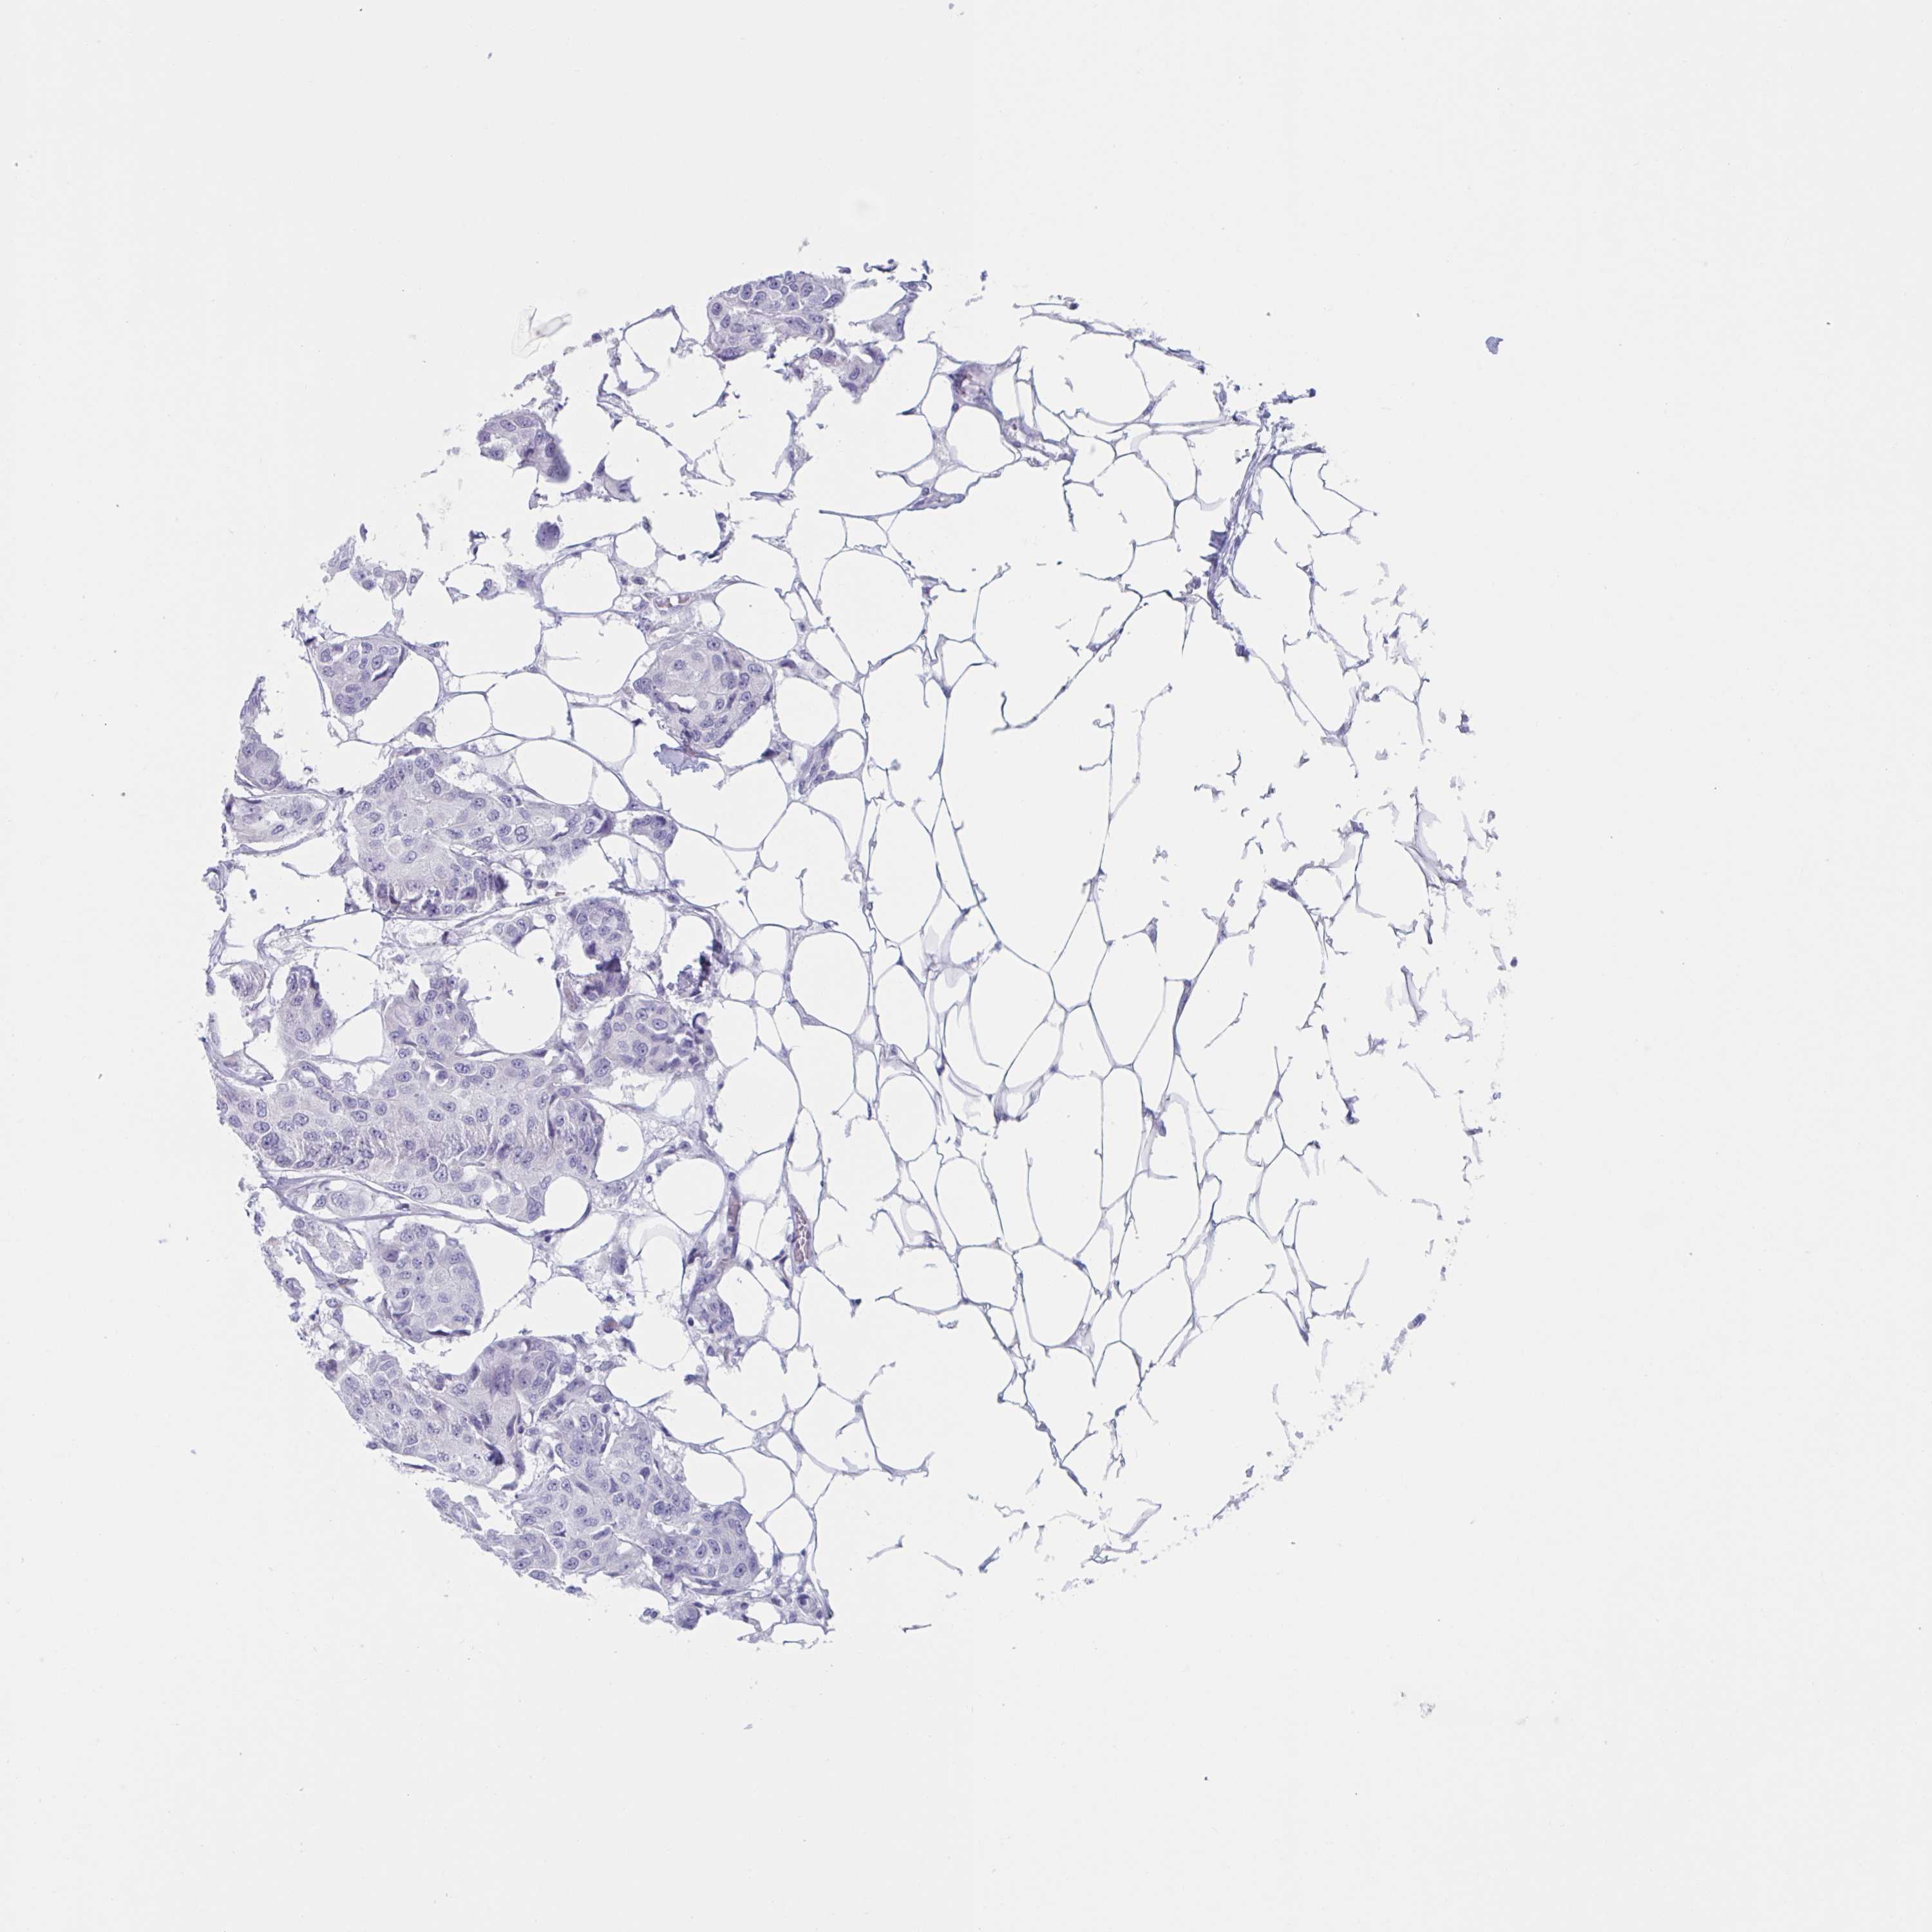

CANCER BREAST CANCER Show tissue menu

Breast cancer

Human cancer

HSD11B2 is potential prognostic, high expression is unfavorable in Breast Invasive Carcinoma (TCGA)